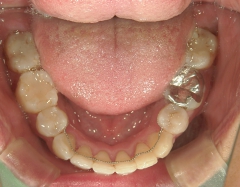

矯正歯科 治療後矯正歯科 全顎ワイヤー矯正 治療後矯正歯科(全顎ワイヤー矯正)治療後

矯正歯科 治療後

矯正_灰色.pngno.31_1962_治療後_上.JPG矯正_灰色.png

矯正_灰色.pngno.31_1962_治療後_下.JPG矯正_灰色.png